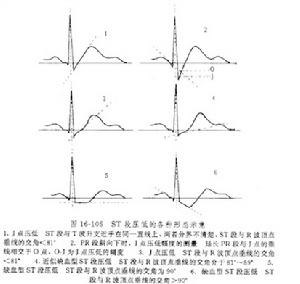

2、運動中及運動後呈水平型或下垂型(即缺血型)ST段壓低≥0.lmV。如果原ST段壓低者,運動後應在原基礎上再壓低0.lmV。

(1)在R波占優勢的導聯上,運動後出現水平型或下垂型別ST段壓低(ST段與R波頂點垂線的交角≥900),超過0.05mV,持續2分鐘者。如果原有ST 段壓低者,運動後在原有基礎上再壓低超過0.O5mV,持續2分鐘。

(2)在R波占優勢的導聯上,運動後出現ST段抬高(弓背向上型)超過0.2mV者。

2、運動後心電圖改變符合下列條件之一者為可疑陽性:

(1)在R波占優勢的導聯上,運動後出現水平型或下垂型ST段壓低0.O5mV或接近0.O5mV及QX/QT比例≥50%,持續2分鐘者。

(2)在R波占優勢的導聯上,運動後出現T波由直立變為倒置,持續2分鐘者。

(3)U波倒置者。

此外,也有人提出運動後R波振幅增高(特別是在ST段壓低的導聯)也是心肌缺血的指標。